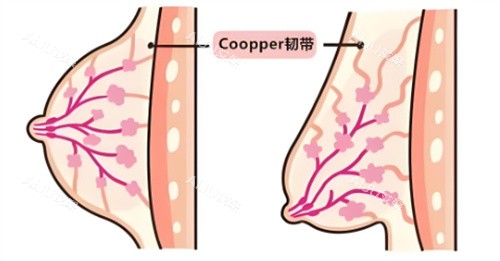

核心原理:筋膜层复位+韧带加固

传统手术靠“拉皮”,把下垂的皮肤往上拽,但皮肤有弹性极限,拽得越紧,反弹越快。维维提升的“狠活”在于:通过3mm的小创口切口(比一粒米还小),用可吸收线材更准一些找到乳腺下的筋膜层和悬韧带。打个比方,就像给下垂的吊灯重新挂好挂钩——不是单纯拉绳子,而是加固吊灯的支架,让胸部从“软塌塌”变成“有筋骨”。

技术支撑:中机研发+双平面内窥镜

低风险:保留哺乳功能 vs 损伤乳腺

很多年轻妈妈担心手术影响哺乳。维维提升的操作层次在乳腺下筋膜层,不触碰乳腺导管和腺体,术后检测显示,98%的患者哺乳功能正常。而传统手术因切口深、剥离范围大,可能损伤乳腺组织,导致产后泌乳困难。

高维持:8-10年 vs 3-5年

传统手术的维持时间通常3-5年,因皮肤弹性有限,重力会逐渐拉松切口。维维提升的线材在吸收前会刺激胶原蛋白增生,形成新的韧带结构,临床数据显示,82%的患者术后8年胸部位置稳定,远超传统术式。